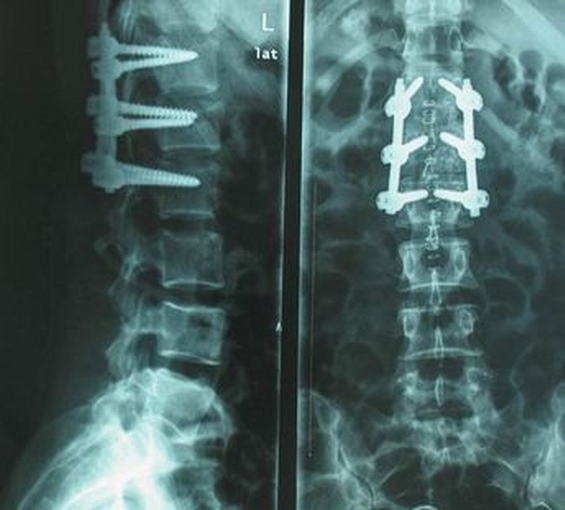

脊柱內(nèi)固定器械

術(shù)后復(fù)查X線片

患者術(shù)后5-7天可下床功能練習(xí)。